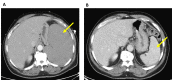

Figure 1. Resolution of splenomegaly with treatment.

Spleen marked by yellow arrows. (A) Before treatment. (B) Five months after treatment.